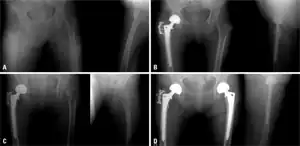

a) Initial radiographs of intertrochanteric fracture b) postoperative - bipolar hemiarthroplasty c) subsequent fracture in left femur neck d) radiograph after a bipolar hemiarthroplasty, the individual began medication for osteoporosis

Conventional radiography is useful, both by itself and in conjunction with CT or MRI, for detecting complications of osteopenia (reduced bone mass; pre-osteoporosis), such as fractures; for differential diagnosis of osteopenia; or for follow-up examinations in specific clinical settings, such as soft tissue calcifications, secondary hyperparathyroidism, or osteomalacia in renal osteodystrophy. However, radiography is relatively insensitive to detection of early disease and requires a substantial amount of bone loss (about 30%) to be apparent on X-ray images.